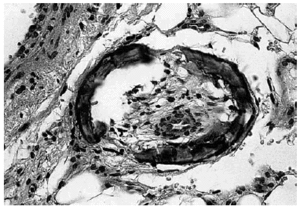

En la exploración se observó, bajo una piel de aspecto clínicamente normal, la presencia de unos nódulos subcutáneos de 3 a 5 cm de diámetro, de consistencia firme, dolorosos a la palpación y localizados en la región abdominal. El examen histológico de la biopsia de uno de estos nódulos evidenció la presencia de múltiples focos de calcificación de la media, con hiperplasia de la íntima, presentes en las arteriolas del tejido celular subcutáneo y de la unión dermohipodérmica (fig. 1).

Fig. 1.--Calcificación de la media e hiperplasia de la íntima en arteriolas del tejido celular subcutáneo (H&E; x200).